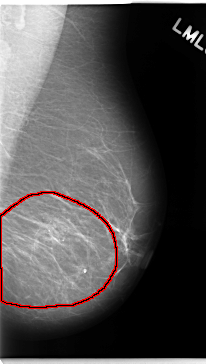

C_0138_1.LEFT_MLO

LEFT_MLO LINES 4720 PIXELS_PER_LINE 2672 BITS_PER_PIXEL 12 RESOLUTION 50 OVERLAY

FILE: C_0138_1.LEFT_MLO.OVERLAY

TOTAL_ABNORMALITIES 1

ABNORMALITY 1

LESION_TYPE CALCIFICATION TYPE AMORPHOUS DISTRIBUTION REGIONAL

ASSESSMENT 5

SUBTLETY 3

PATHOLOGY MALIGNANT

TOTAL_OUTLINES 1

BOUNDARY